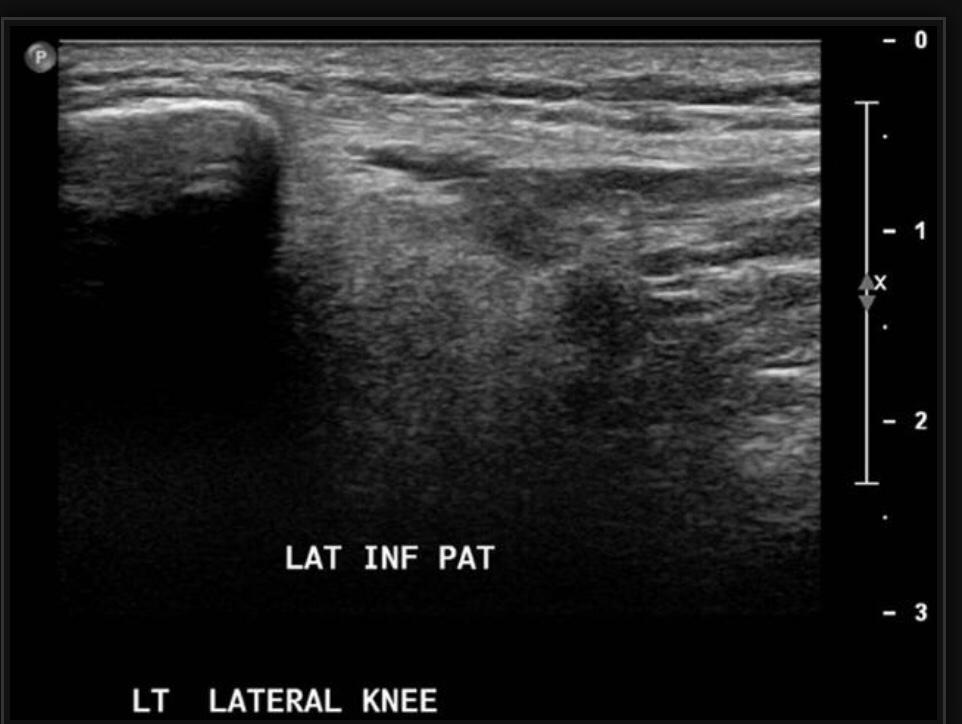

PATELLAR TENDON-LATERAL FEMORAL CONDYLE FRICTION SYNDROME

Patellar tendon-lateral femoral condyle friction syndrome, also known as Hoffa fat pad impingement syndrome, is a common cause of anterior knee pain in active individuals. It is thought to be due to patella maltracking or imbalance of the forces between medial and lateral vastus muscles causing impingement of the superolateral aspect of Hoffa fat pad between the inferior patella and the lateral femoral condyle.

Patients with Hoffa syndrome would present with acute or chronic sharp pain below the patella which is worsened by activities like walking, prolonged standing, wearing high heel shoes or any other activity that puts the knee into full extension. On examination, there may be swelling in the infrapatellar region, with point tenderness at the inferior pole of the patella.

The diagnosis is classically made with MRI and usually occult on radiography and CT. MRI findings include focal area of high T2 signal (edema) at the inferolateral aspect of the patellofemoral joint, within the superolateral portion of the infrapatellar fat pad. A cystic lesion can sometimes be found between the lateral femoral condyle and the lateral retinaculum. Associated findings include lateral patellar subluxation and patella alta (Insall-Salvati ratio greater than 1.2) which are found in around 90% of cases. Conservative treatment is usually successful, although full recovery may take time.